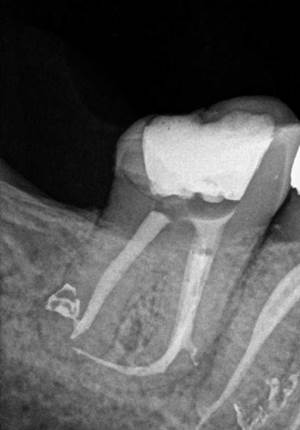

2. Retratamiento con lima separada en conducto

Radiografía de retratamiento de endodoncia donde en la inicial se observa una lima separada en un conducto. En la final se ve cómo hemos sobrepasado la lima y hemos conseguido obturar el sistema de con ayuda de la magnificación.